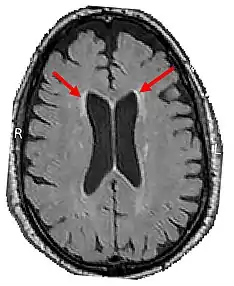

Brain CT of brain showing white matter lesions (indicated by the red arrows)

4. Brain CT/MRI findings:

1. Bilateral Cerebral white matter lesions[10]

2. Thinning of the Corpus Callosum[10]